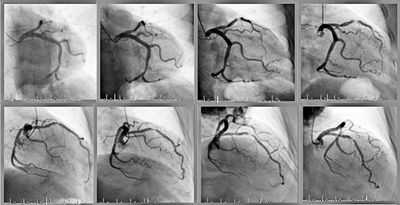

Ангиографический снимок

Представленный вид исследования может визуализировать сосуды любых размеров (от аорты до мельчайших капилляров) и все системы и органы человеческого организма. Кроме этого, ангиография сосудов зачастую применяется перед осуществлением хирургических вмешательств для предоперационной подготовки и диагностики.

Ангиография сердца

Показанием для ангиографии сосудов сердца (коронарографии) являются нижеперечисленные заболевания:

- Инфаркт миокарда в анамнезе;

- Прогрессирующая стенокардия;

- Нарушения сердечного ритма;

- Стенокардия, при которой прием нескольких препаратов не дает желаемого эффекта и другие состояния.